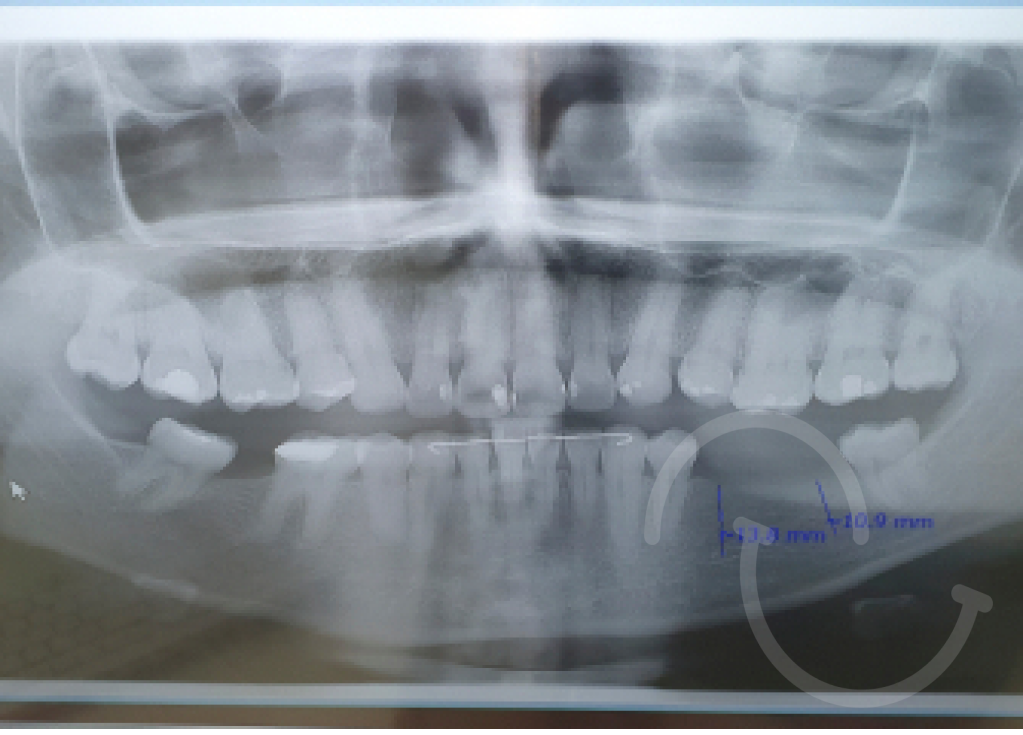

La reconstrucción de sonrisas mediante intervenciones quirúrgicas es un proceso complejo que a menudo se realiza en situaciones en las que la estructura ósea es insuficiente o cuando es necesario corregir problemas en el tercio inferior del rostro. Este tipo de procedimientos generalmente involucra a profesionales de la odontología y cirujanos maxilofaciales que trabajan en conjunto para lograr resultados estéticos y funcionales.

Injertos óseos: Cuando la estructura ósea es insuficiente para sostener implantes dentales o corregir deformidades, se pueden realizar injertos óseos. Esto implica tomar hueso de otra parte del cuerpo del paciente o utilizar material de injerto sintético para fortalecer la mandíbula o el maxilar.

Implantes dentales: En casos de pérdida dental, los implantes dentales pueden ser utilizados para reemplazar dientes ausentes. Estos implantes son insertados quirúrgicamente en el hueso maxilar o mandibular y actúan como raíces artificiales para sostener las coronas dentales.

Es importante destacar que estos procedimientos suelen ser personalizados según las necesidades específicas de cada paciente. Además, el proceso de rehabilitación puede requerir la colaboración de varios profesionales de la salud, como ortodoncistas, periodoncistas, y cirujanos maxilofaciales, para lograr resultados exitosos y duraderos.